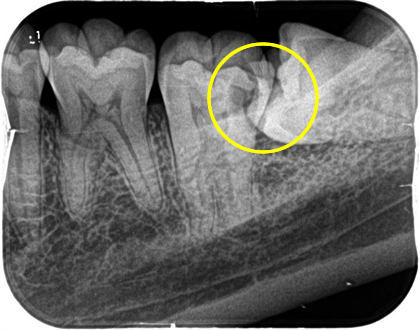

親知らずが傾斜して前の歯に引っかかっているケースは、前の歯が虫歯になりやすいので、症状が無くても早期に抜歯した方が良いことがあります。

上の写真のケースでは、親知らずが横を向いて前の歯との間に食渣が非常に挟まりやすい状態になっていました。患者さんご本人も気になっていましたが放置されていたため、左下の歯が痛くなり、来院された時には親知らずの前の歯が神経に達するほどのむし歯になっていました。

ここが虫歯になると、神経に近接しているため治療が困難になり、神経の治療を行っても予後が悪くなります。